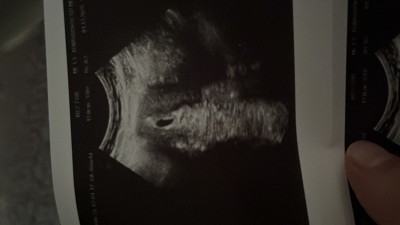

Keseme bakarmısın armut şekli gibi yuvarlak olmuyormu normalde böyle olan varmı?

Gebelik haftası 5 hafta 4 gün

Öncelikle kese şeklinin cinsiyet ile uzaktan yakından alakası yok.

Haftanız küçük olduğu için doktor keseyi ayırt etmek için cihazı çok bastırmış olması lazım ki böyle şekile girmiş.